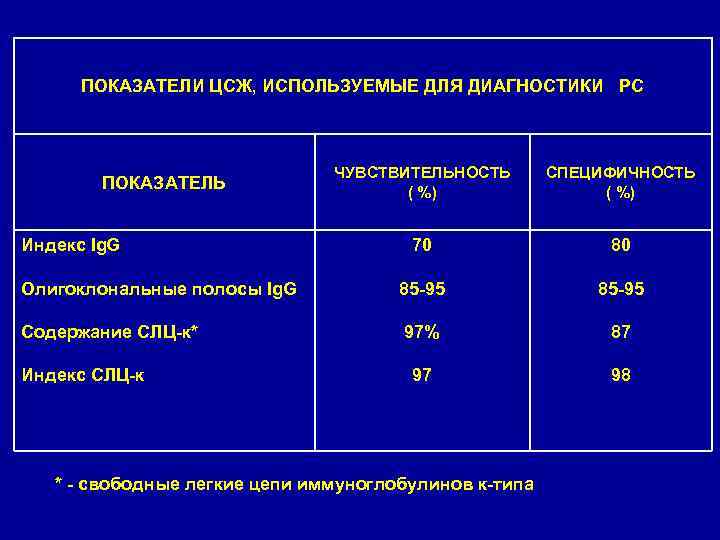

• Исследование изменений в спинномозговой жидкости (СМЖ) также помогает подтвердить диагноз PC. • В начальной стадии заболевания и ЛАБОРАТОРНЫЕ МЕТОДЫ ИССЛЕДОВАНИЯ в периоды обострения отмечается плеоцитоз (более 5 лимфоцитов в 1 мкл). У 75% больных повышен уровень гамма-глобулинов, несколько увеличено содержание общего белка. • При электрофорезе концентрированной цереброспинальной жидкости у 85 -95% больных PC выявляются олигоклональные Ig. G; этот тест можно использовать для подтверждения PC, так как он часто положителен на ранней стадии заболевания. • Аналогичной информативностью обладает выявление в СМЖ повышенного уровня свободных легких каппа-цепей иммуноглобулинов с помощью иммуноферментного анализа.

ПОКАЗАТЕЛИ ЦСЖ, ИСПОЛЬЗУЕМЫЕ ДЛЯ ДИАГНОСТИКИ РС ПОКАЗАТЕЛЬ Индекс Ig. G ЧУВСТВИТЕЛЬНОСТЬ ( %) СПЕЦИФИЧНОСТЬ ( %) 70 Олигоклональные полосы Ig. G 85 -95 80 85 -95 Содержание СЛЦ-к* 97% 87 98 Индекс СЛЦ-к * - свободные легкие цепи иммуноглобулинов к-типа